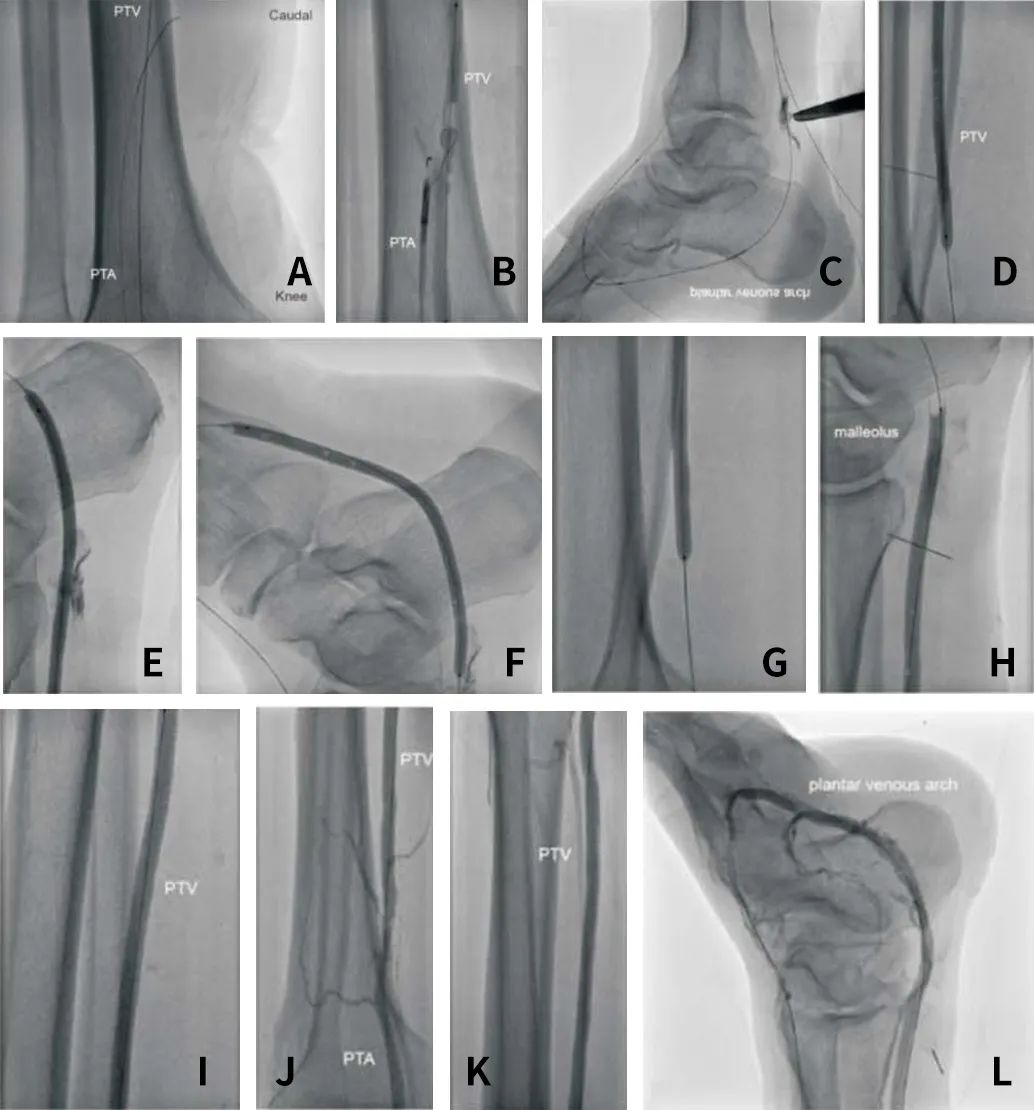

1、动脉:将6F鞘顺行插入左股总动脉(LCFA),使用CXI支持导管推送PT2导丝至左胫后动脉(LPTA),改用V18导丝增强支撑性。

2、静脉:在超声引导下于踝部向左胫后静脉(LPTV)置入5F鞘管,置入5.0*80 mm Pacific球囊(图2A)。

3、建立通路:使用V18导丝及Outback Reentry装置,经左胫后动脉(LPTA)穿刺LPTA-LPTV(图2B),导丝延伸至足底静脉弓和左胫前静脉,造影确认(图2C)。以10atm压力使用4.0*80mm Pacific球囊预扩张左胫后静脉(LPTV) (图2D、2E)和左足底深静脉(图2F)。

4、植入支架:随后分别于LPTA-LPTV动静脉分流处、左胫后静脉(LPTV)和足底深静脉置入5.0*50mm、5.0*150mm、5.0*100mm Viabahn肝素涂层覆膜支架(图 2G、2H、2I)。

5、支架后扩:使用4.0*120mm 和5.0*80mm Pacific球囊在16 atm压力下对支架进行后扩张。

6、最终造影显示:LPTA-Viabahn-LPTV-足底深静脉弓顺向血流良好(图 2J,2K,2L)。术后患者伤口愈合良好,且随访1年超声复查显示各动脉及动脉化静脉血流良好,Viabahn覆膜支架通畅,患者术后3年内未发生左下肢截肢。

图2. 经皮深静脉动脉化过程。